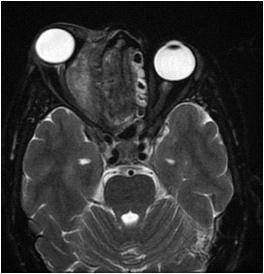

Spontaneous or acute ICH appears on the CT head as an area of hyperdensity within the Parenchyma (Fig 2) or extended into the ventricle (Fig 3), with surrounded hypodense perivascular oedema.

Fig 2 — Computed tomography axial image of head demonstrating an illdefined ovoid, hyperdense focus at left thalamic nucleus level, in keeping with a hematoma. (white arrow)